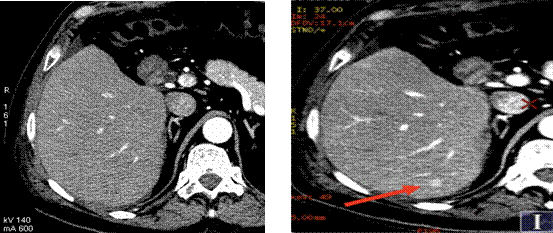

傳統(tǒng)CT成像,未顯示病灶 40keV單能量下診斷病灶

高能量X射線可以去除高密度金屬引起的偽影

常規(guī)CT 寶石能譜CT

140keV能量成像可以除去金屬引起的偽影,更加清晰觀察術(shù)后情況